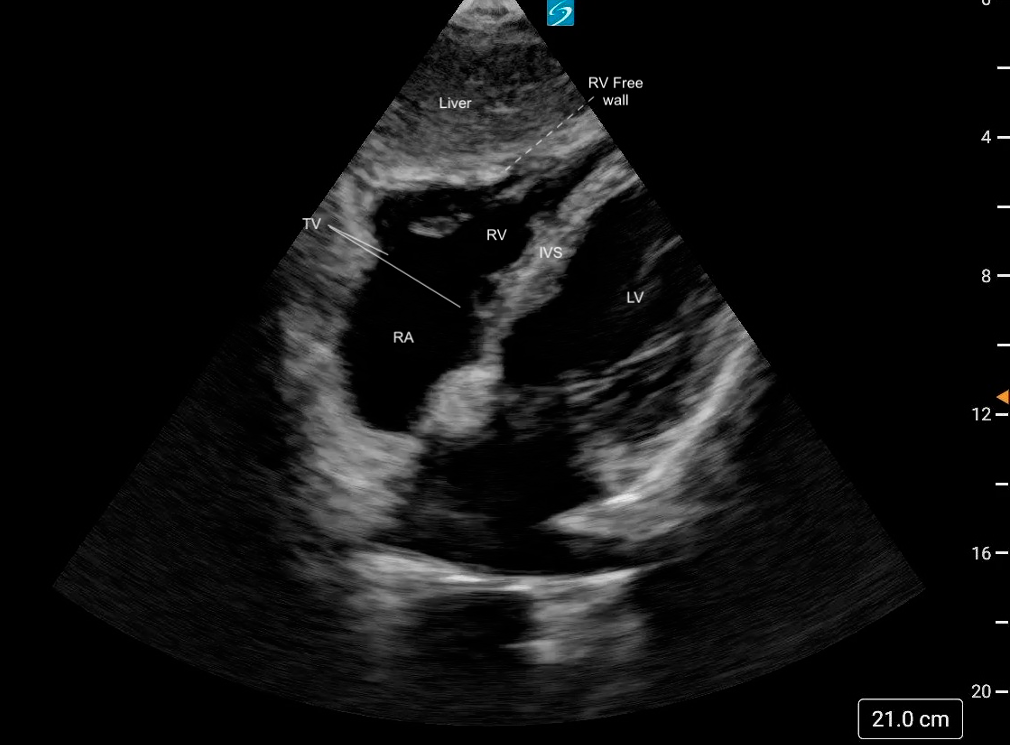

Subcostal Four Chamber

What am I Looking at?

The subxiphoid 4 Chamber view can be used to assess ventricular function, particularly during emergent situations, when access to the other windows is limited.

The left ventricle is seen in the far field with the septal and lateral walls in view. The RV is seen more anteriorly.

Figure 25. Subxiphoid 4 chamber with the LV walls labeled